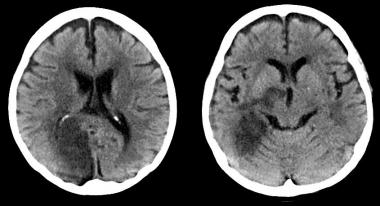

La obstrucción mayor del 50% de la carótida interna extracraneal no limitó el beneficio del tratamiento intraarterial agudo en el ictus isquémico de causa intracraneal. Annals of Internal Medicine, 23 de mayo de 2017